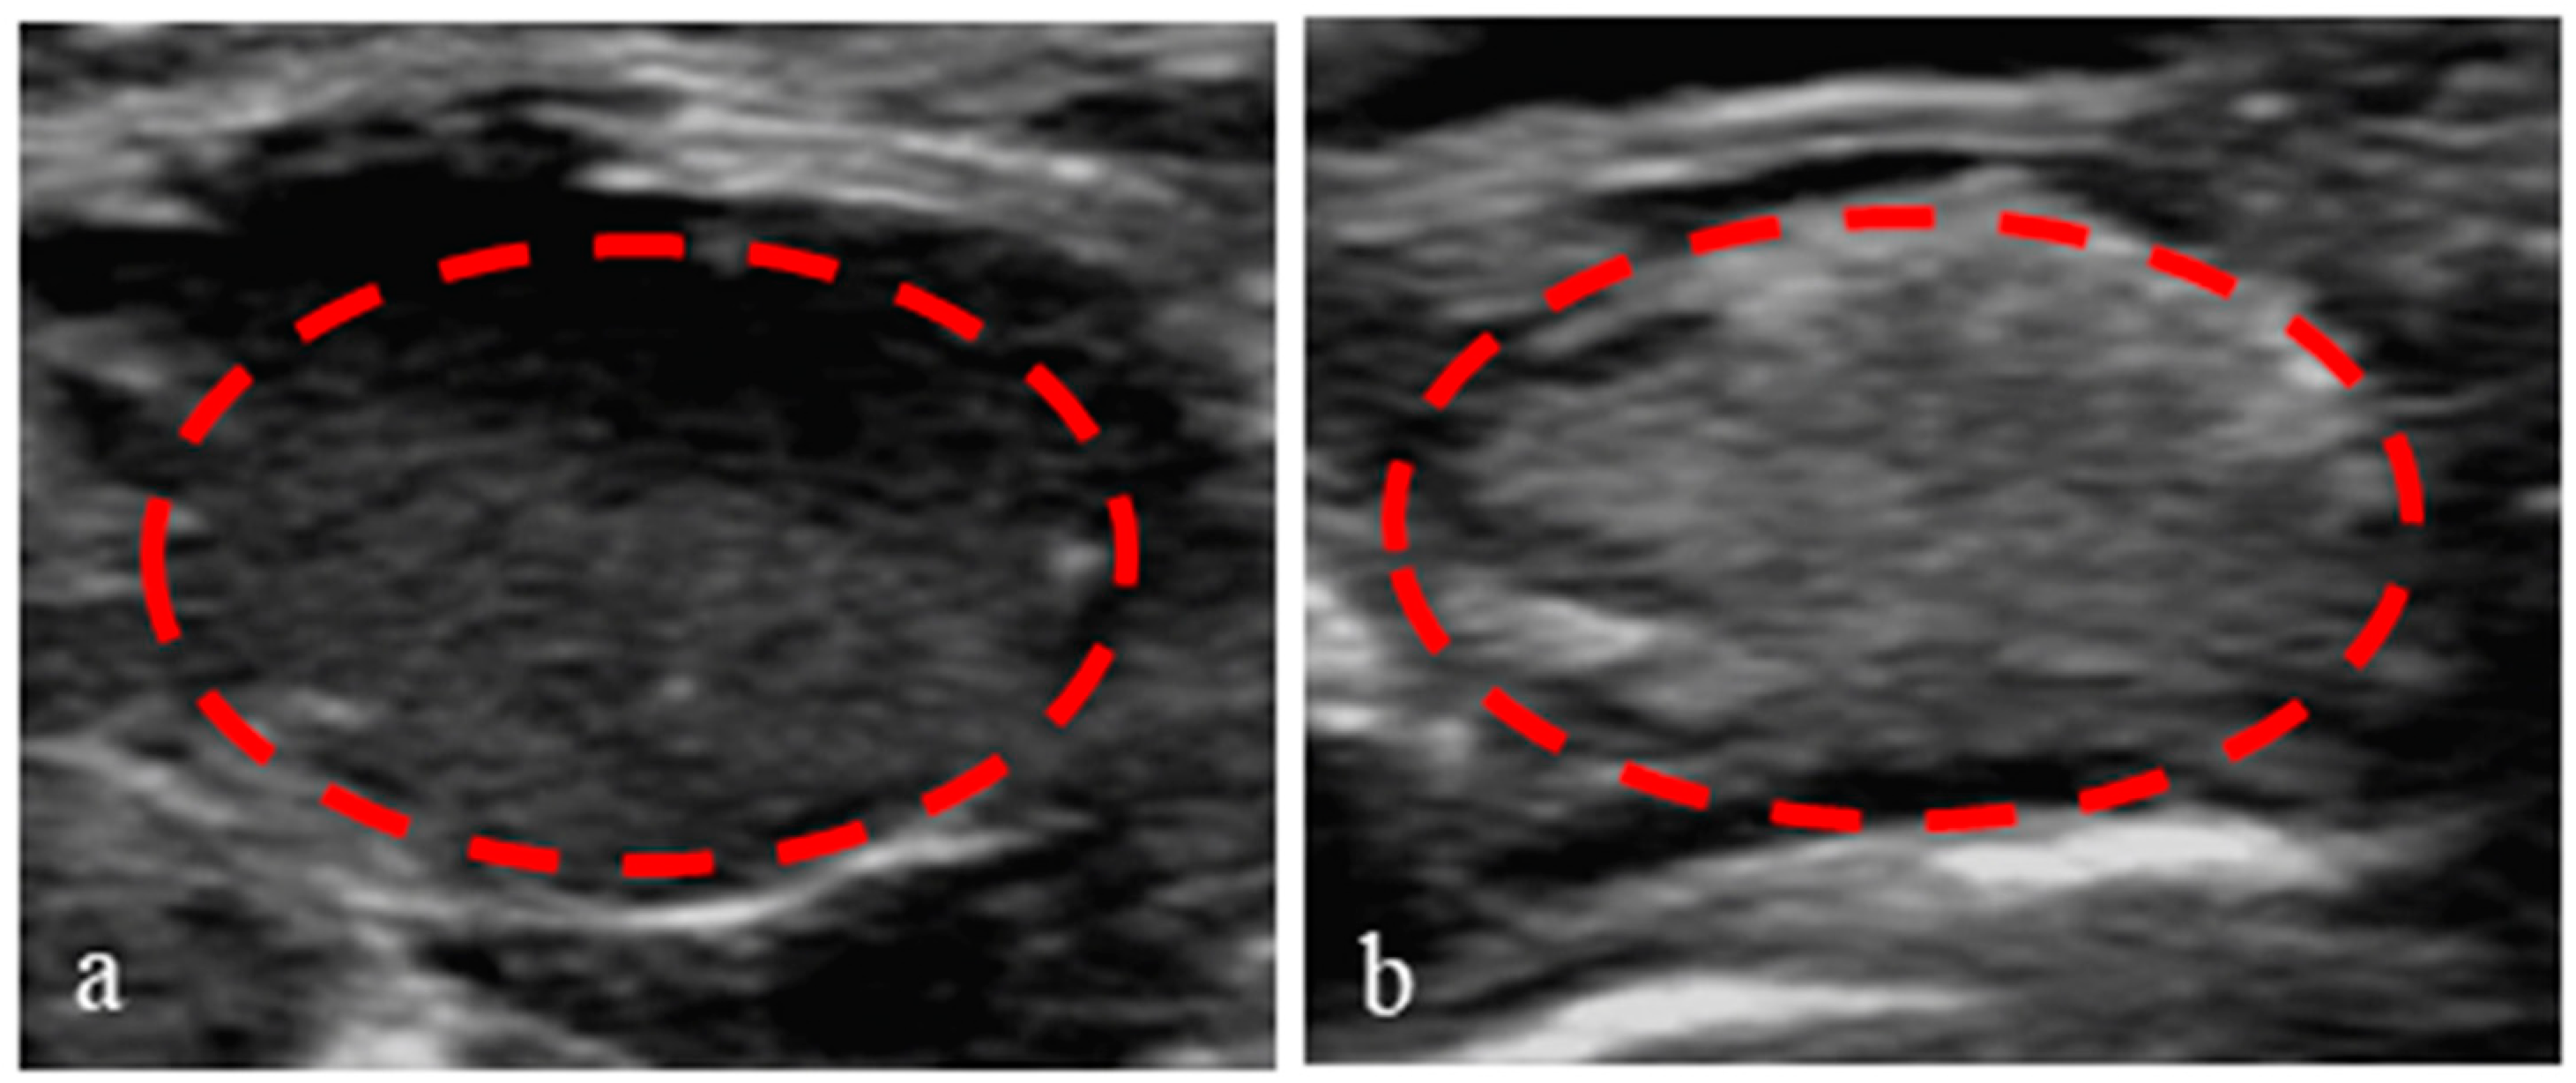

3.8. Application of Nanoparticles in Ultrasound-Enhanced Imaging of Tumors